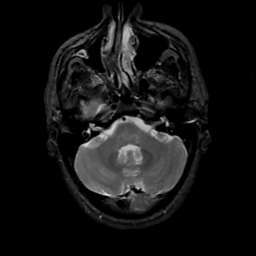

MR Study #8, March 31, 1991 -- Slice #11